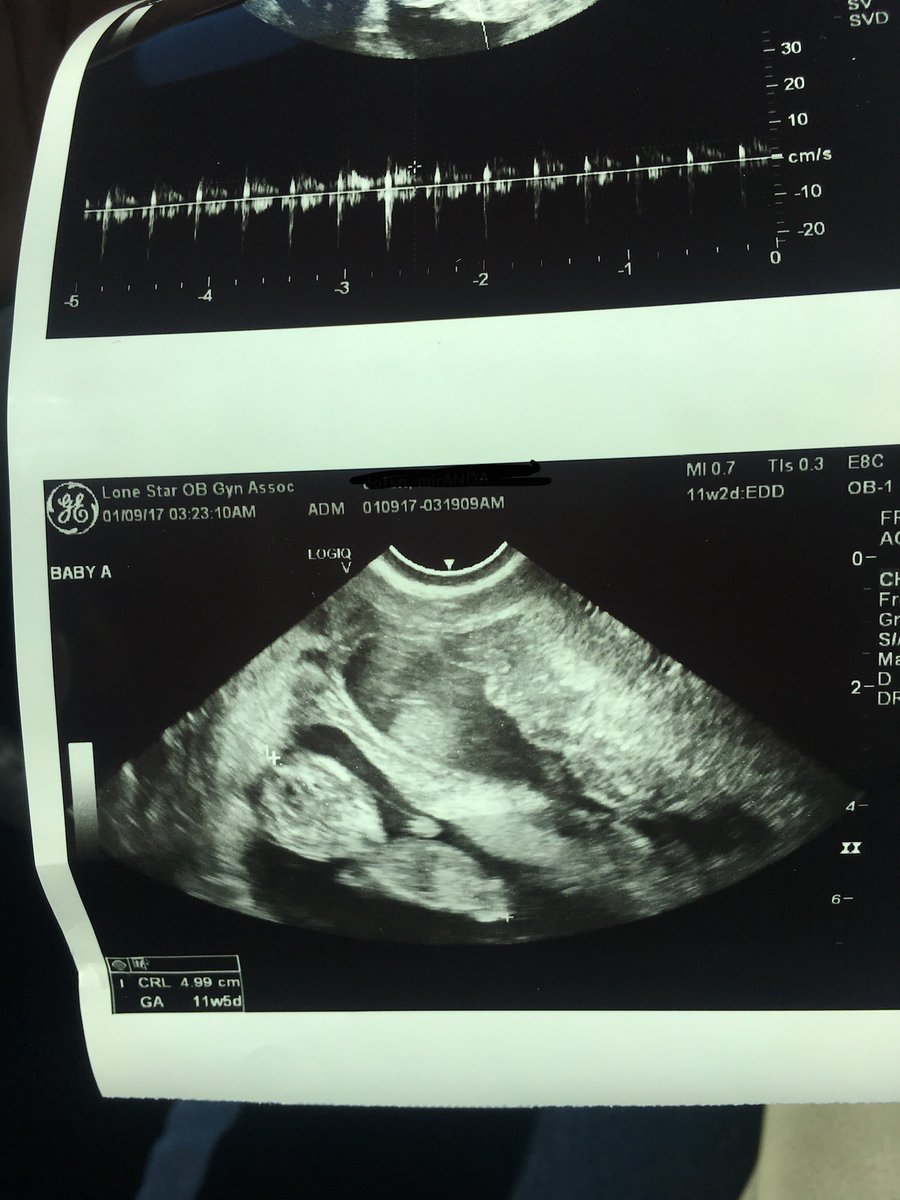

I’ve blocked my name and birthday out for privacy but that’s also not what a 15 week old fetus would look like. Here’s mine at 11 weeks

And here’s 23 weeks. There’s no way that fetus was 15 weeks.